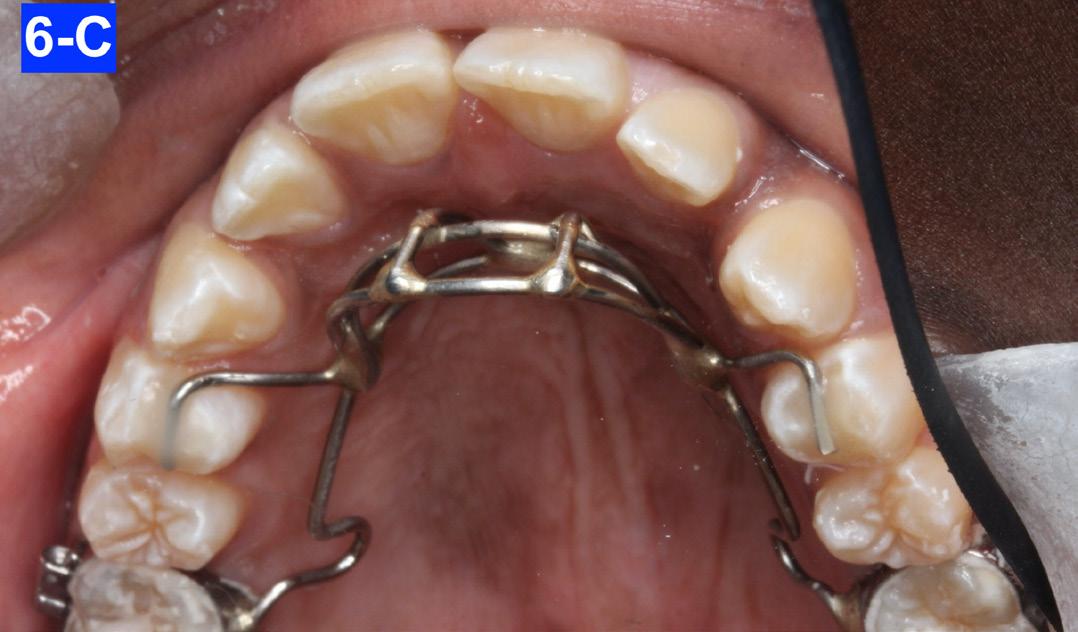

There was an eleven-month hiatus between the examination and commencement of the treatment. Therefore, the patient was already 14-years old. The patient, and her parent, declined the mandibular lingual and maxillary labial frenectomy. However, they proceeded with the OMT. Once the patient was able to repeatedly demonstrate the correct swallowing pattern upon unprovoked observation, the fixed habit breaker was inserted in the maxilla. It was cemented on the first molars and bonded on the first bicuspids (Figure 6-A, B, C).

Fig. 6-A: Maxillary habit breaker

Fig. 6-B: Habit breaker in situ I

Fig. 6-C: Habit breaker in situ II